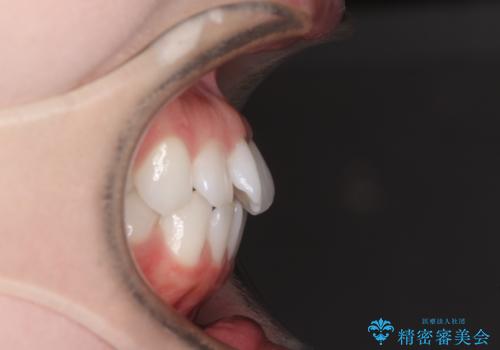

- 海外留学を前に上下のデコボコと奥歯の咬み合わせを改善したいとのことで来院された患者様です。

期間が限られていたため、ワイヤー装置による矯正治療を行うこととしました。